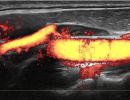

Το Υπερηχογράφημα Λεμφαδένων Τραχήλου προσφέρει μια εμπεριστατωμένη εικόνα των λεμφαδένων, με χρήση της προηγμένης τεχνολογίας των ειδικών κεφαλών υψηλής συχνότητας, Έγχρωμου Doppler, Power Doppler και B-Flow, καθώς και της Ελαστογραφίας. Με αυτές τις τεχνικές είναι δυνατή η γρήγορη και αξιόπιστη αξιολόγηση της μορφολογίας των λεμφαδένων και η αναγνώριση των χαρακτηριστικών τους με μεγάλη ακρίβεια.